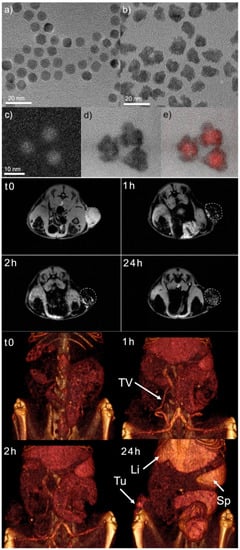

- Efremova, M.V.; Naumenko, V.A.; Spasova, M.; Garanina, A.S.; Abakumov, M.A.; Blokhina, A.D.; Melnikov, P.A.; Prelovskaya, A.O.; Heidelmann, M.; Li, Z.A.; et al. Magnetite-Gold Nanohybrids as Ideal All-in-One Platforms for Theranostics. Sci. Rep. 2018, 8, 11295. [Google Scholar] [CrossRef] [PubMed]

| Fe3O4@Au | x | Core/Shell | 30 | 121 ± 5 nm/ −19.1 ± 3.3 mV | DSPE-PEG-COOH | - | 4T1-GFP bearing mice | [46] | |||||